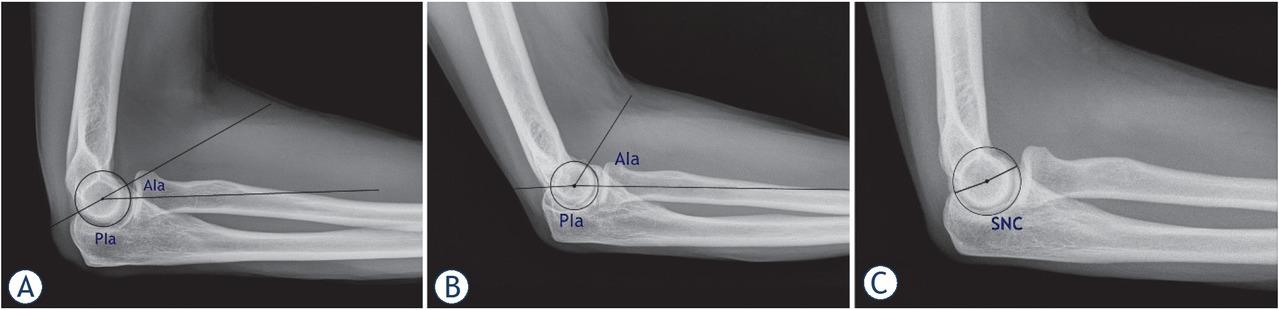

Standard antero-posterior and lateral x-ray views were obtained. Unsatisfactory films were repeated in order to maintain consistency. Digital radiograph images were analyzed using Agfa IMPAX 6 software (Agfa HealthCare, Belgium). Broberg and Morrey (BM) as well as Hasting and Rettig (HR) classifications of elbow osteoarthritis were used to assess elbow joint’s degenerative changes.6,7 Sigmoid notch coverage (SNC) measurement was performed as described by Goldfarb et al., as a line connecting the center of the circle, fitted to sigmoid notch, to both the tip of the olecranon and coronoid (Figure 1C).8 Measurements of the Anterior Impingement angle (AIa) and Posterior Impingement angle (PIa) were obtained on lateral x-ray images as previously described by Meglic and Zupanc.9 The angle between the centralized ulnar direction line and the line between the center of rotation (COR) and the tip of the coronoid presents AIa. The angle between the centralized ulnar direction line and the line between the COR and the tip of the olecranon presents PIa (Figure 1A, B).9 For reliability evaluation, two upper extremity surgeons (OZ, UM) and one resident after radiological training (NK), independently evaluated each radiograph for radiographic measurements of AIa and PIa. Each evaluator re-measured both parameters after an interval of at least 2 weeks, a period used in other reliability studies in upper extremity.1,10 The examiners were blinded to their previous measurements.

Radiographic measurements: (A) Anterior Impingement angle (AIa) and Posterior Impingement angle (PIa) in normal group, (B) AIa and Pia in EBI group, (C) sigmoid notch coverage angle (SNC) in normal group.